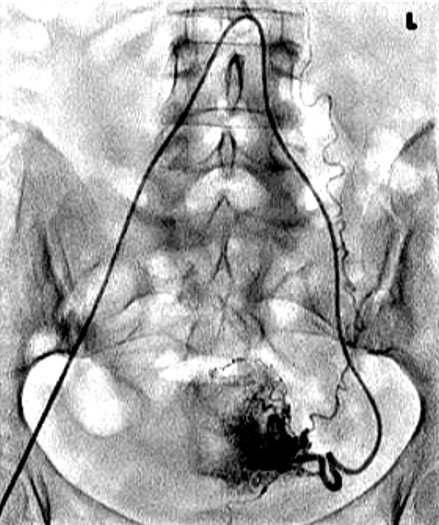

![]() 双侧子宫动脉发育不良 双侧卵巢动脉栓塞术 - 500 - 900 微米 未出现卵巢功能衰竭 ![]() 约10%-15%的患者在接受UAE后未见明显改善,其中一些病例可能是因为卵巢动脉提供了额外的血供。 文章通过回顾六例患者的治疗经验,探讨了卵巢动脉栓塞术(OAE)作为子宫动脉栓塞术(UAE)补充疗法的可行性和效果。研究发现,OAE能够成功地使肌瘤缺血坏死,并且大多数患者在术后症状有所改善。尽管存在技术挑战,但OAE似乎是安全有效的。此外,所有接受OAE治疗的患者均保留了正常的月经周期,这表明该手术可能不会导致卵巢功能丧失。然而,由于样本量较小,目前的研究结果尚不足以得出明确结论,需要进一步的研究来验证这些发现。 ![]() 评估在有卵巢动脉参与供血的症状性子宫肌瘤患者中,进行卵巢动脉栓塞术的安全性及临床结局。 共13名患者,均有症状性子宫肌瘤,且MRI或血管造影显示有卵巢动脉参与供血。并在初次或二次进行补充卵巢动脉栓塞术。

所有年龄超过 40 岁的患者, 卵巢受损 14%-43% 研究中闭经发生率(15%)与单纯UAE报告相似,可能与患者年龄(≥45岁)及卵巢储备自然下降有关。 ![]() 50岁,长期因子宫肌瘤导致月经出血过多,痛经和贫血。 子宫肌瘤栓塞术前,显示双侧子宫动脉发育不全,子宫肌瘤双侧卵巢动脉。 经皮股动脉穿刺双侧卵巢动脉栓塞,先500μm-700μm emboSphere 微球 术后4周,和6月的中短期随访,月经正常,子宫容积减少,贫血纠正,无卵巢功能衰竭。但看起来非灌注容积较少。 术后9月,由于子宫肌瘤持续存在,患者自己希望绝经,行全子宫和双侧卵巢切除术 术后病理,子宫内可见栓塞微粒伴有坏死,卵巢内也见栓塞微粒,但卵巢功能未受损。